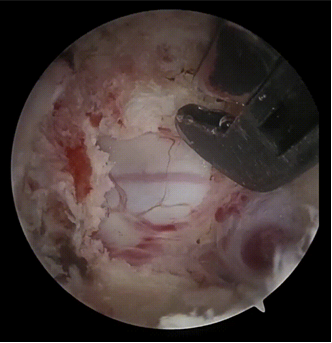

在完成了缜密的术前准备包括与患者家属充分沟通后,姜主任及团队在麻醉手术科的密切配合下开始了这场“刀尖上的舞蹈”。由于患者的齿状突游离且上颈段脊髓严重受压,麻醉后由仰卧改为俯卧的过程就十分危险,姜主任指挥团队小心翼翼地为患者完成了翻身,心电监视一切正常。由于上颈椎的特殊性,C1-2水平脊髓无骨性覆盖,易定位错误及穿刺误伤脊髓,团队也顺利地精准定位完成套管放置。手术在患者的颈后部做了两个各1cm的微小切口,精准到达目标区域后建立操作与观察通道,在高清内镜直视下磨钻去除部分C1后弓及C2骨组织,显露病变部位并进行射频止血,分离组织,切除增生的骨组织并不断重复。这一过程是对术者心理与体力的双重考验,团队精神高度集中,手术前后累计4个小时。

图2:术中见C1-2脊髓硬膜膨隆